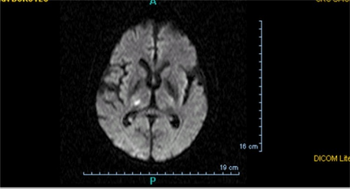

Lacunar infarct on brain MRI

In terms of the diagnosis of a stroke of this nature, the following is done:[12]

• CT scan

• MRI

• CT angiogram